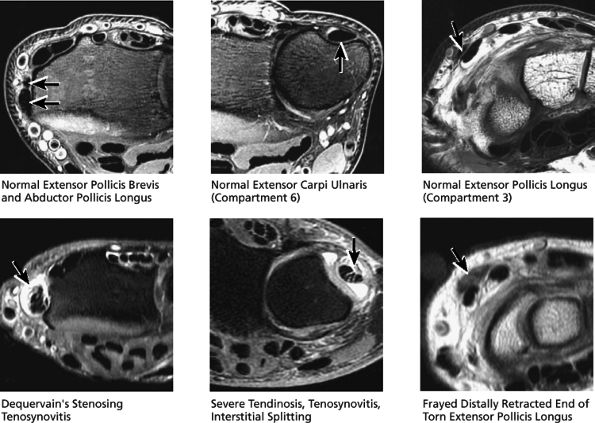

Compartment 1 lies along the lateral aspect of the radius and contains the extensor pollicis brevis and the abductor pollicis longus.

Compartment 3 contains the extensor pollicis longus.

Compartment 6 contains the extensor carpi ulnaris, which runs within the groove formed by the ulnar styloid.

radial aspect of the distal forearm (proximal to the wrist), where the first compartment muscles cross over the second extensor compartment tendons. Tendinosis and tearing of the extensor carpi ulnaris (in compartment 6) is also common and presents as dorsal ulnar-sided pain. The extensor pollicis longus (in compartment 3) can also occasionally tear. The distally retracted, thickened, and frayed end of the torn extensor pollicis longus is often visualized at the level of the proximal carpal row, where the extensor pollicis longus tendon crosses dorsal to the extensor carpi radialis brevis and longus tendons.